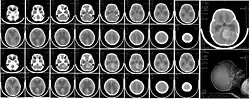

| CT scan, showing a tumorous mass in the posterior fossa, giving rise to obstructive hydrocephalus, in a six-year-old girl | |